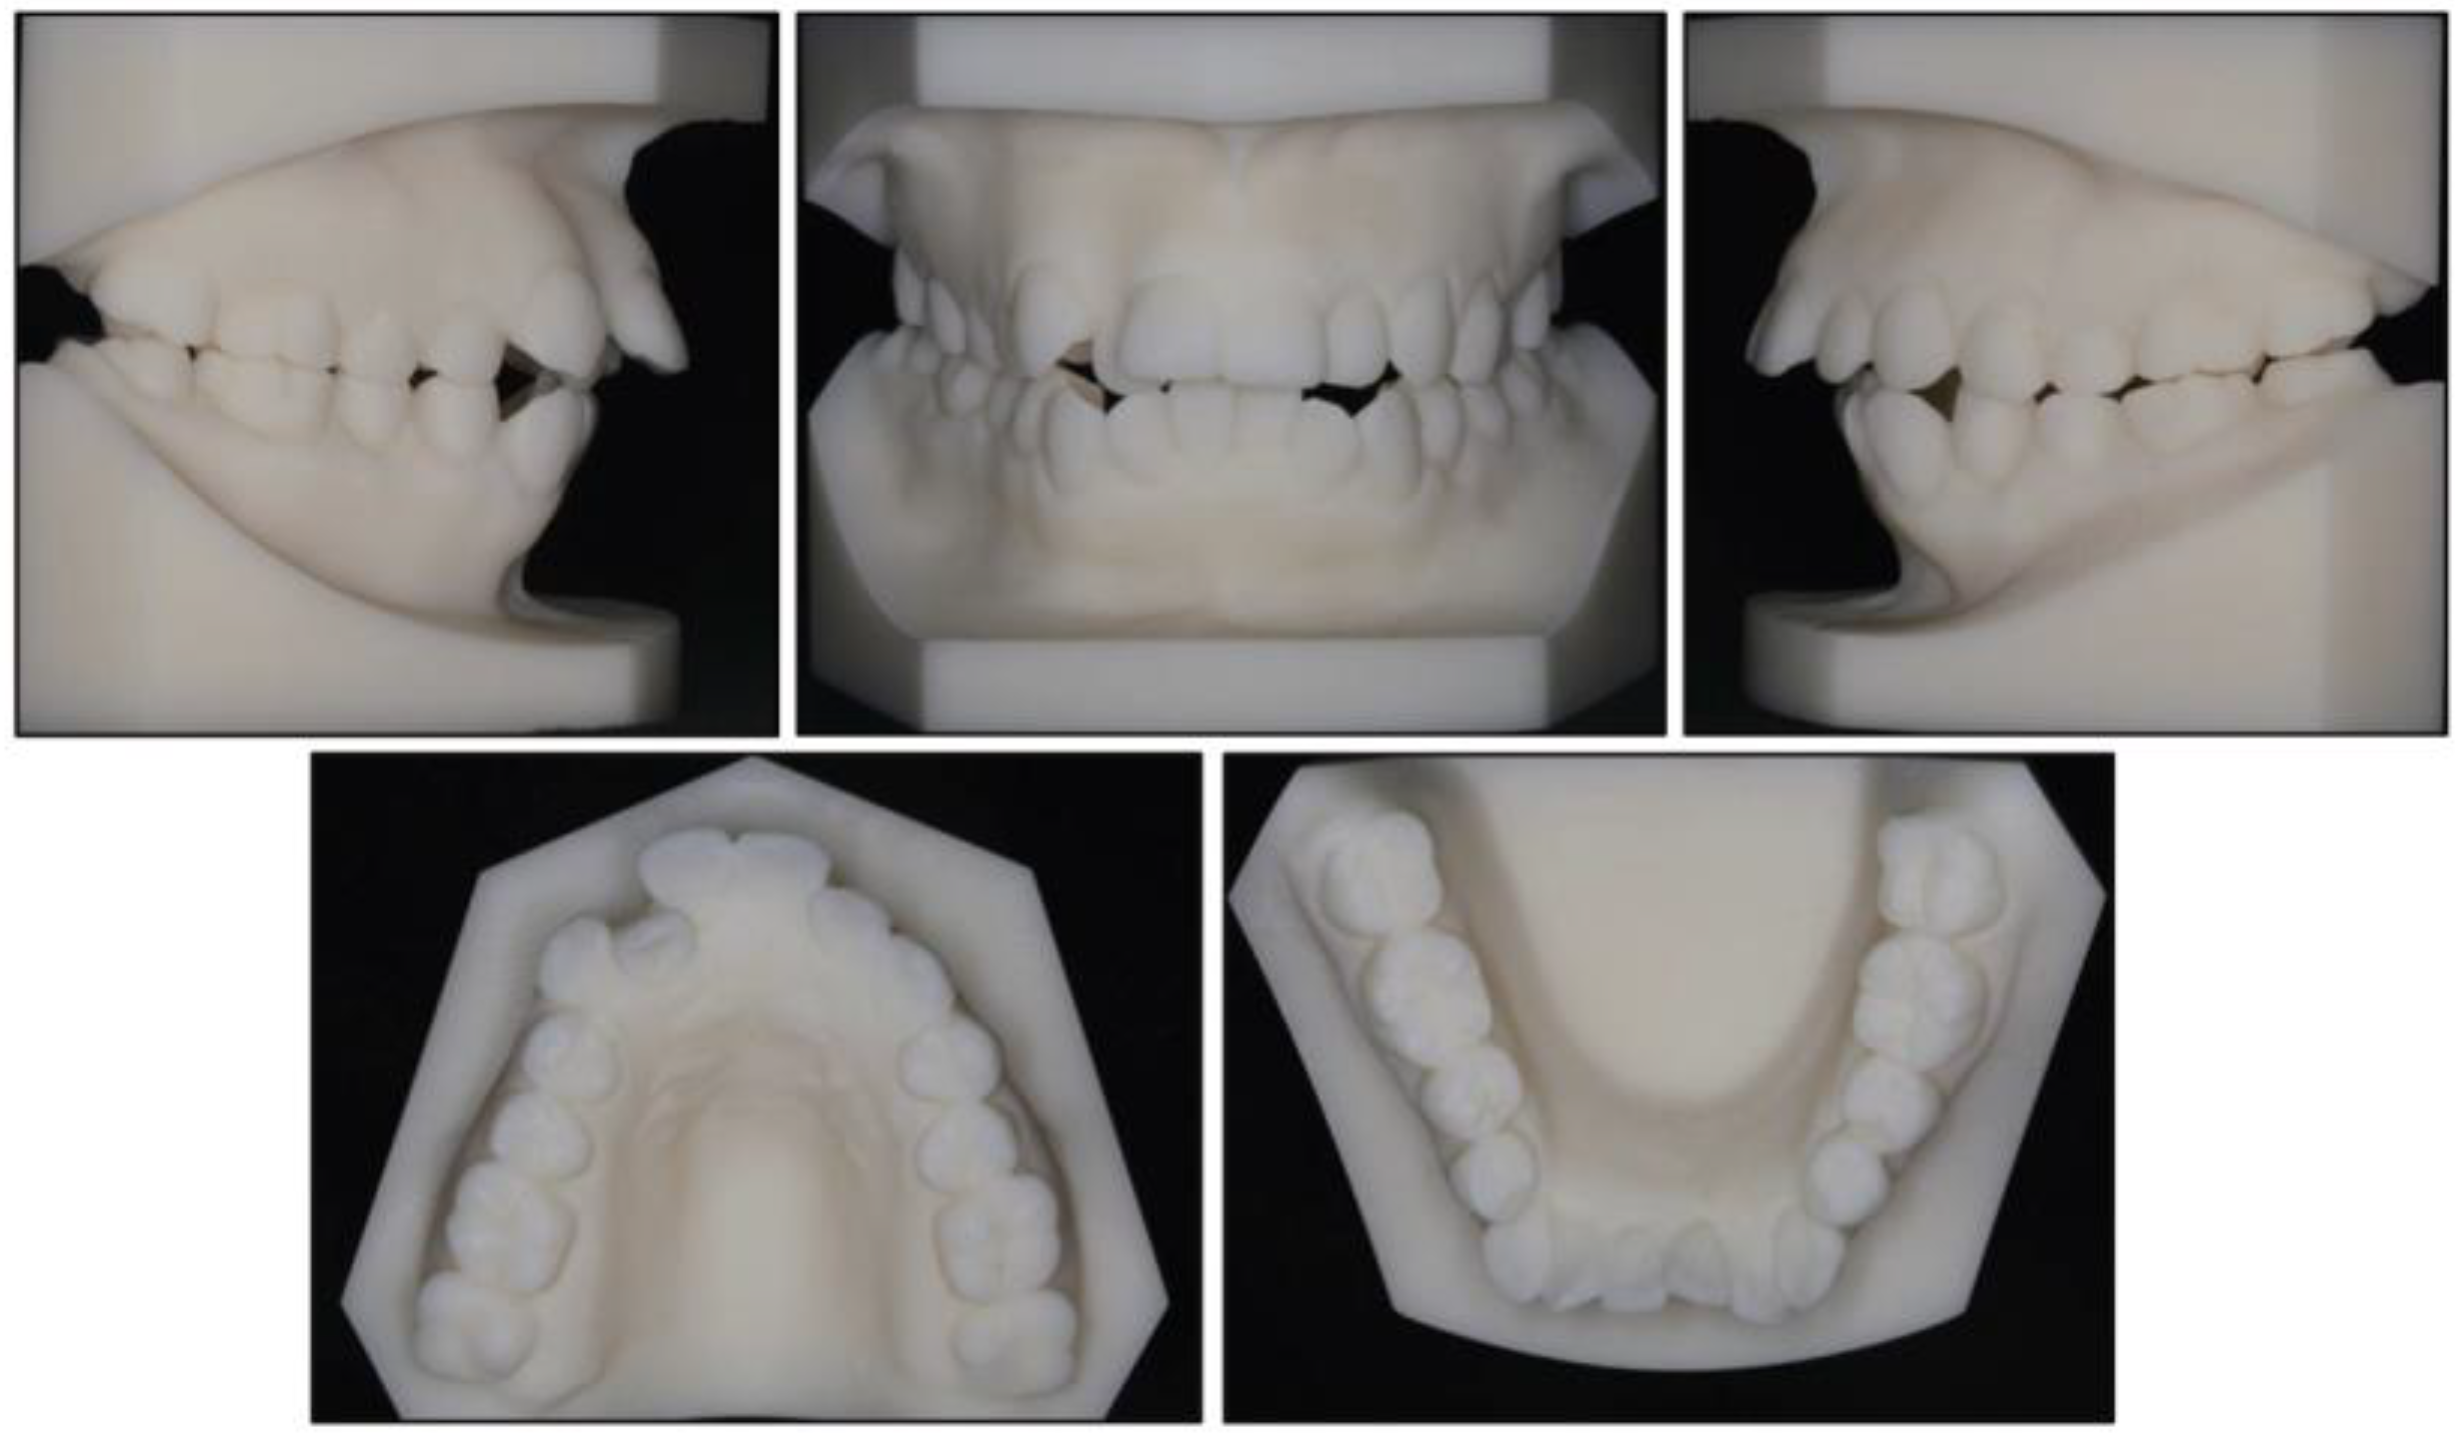

2. Case Report

2.1. Diagnosis and Etiology